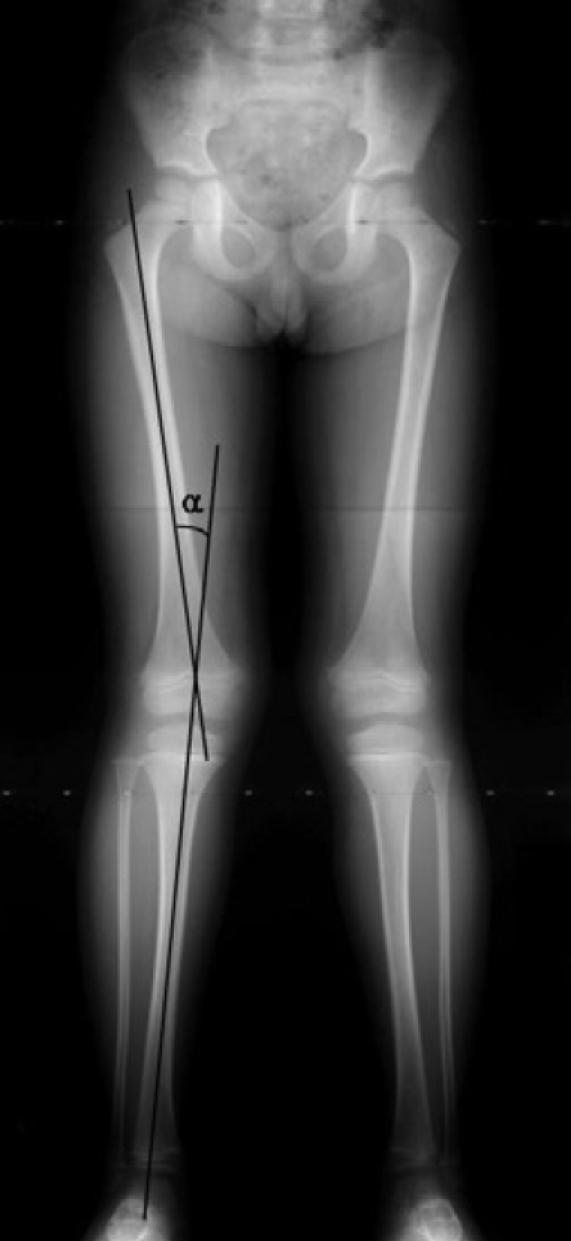

This study was performed to identify the chronological changes of the knee angle or the tibiofemoral angles in normal healthy Korean children. Full-length anteroposterior view standing radiographs of 818 limbs of 452 Korean children were analyzed. The overall patterns of the chronological changes in the knee angle were similar to those described previously in western or Asian children, but the knee angle development was delayed, i.e., genu varum before 1 yr, neutral at 1.5 yr, increasing genu valgum with maximum a value of 7.8 degrees at 4 yr, followed by a gradual decrease to approximately 5-6 degrees of genu valgum of the adult level at 7 to 8 yr of age. These normative data on chronological changes of knee angles should be taken into consideration when evaluating lower limb alignment in children.

本研究旨在确定正常健康韩国儿童膝关节角度或胫股角随时间的变化。对452名韩国儿童的818条肢体的全长前后位站立位X线片进行了分析。膝关节角度随时间变化的总体模式与先前在西方或亚洲儿童中描述的相似,但膝关节角度发育延迟,即1岁前膝内翻,1.5岁时为中立位,4岁时膝外翻增加,最大值为7.8度,随后逐渐减小,在7至8岁时达到成人水平的约5 - 6度膝外翻。在评估儿童下肢对线时,应考虑这些关于膝关节角度随时间变化的规范数据。